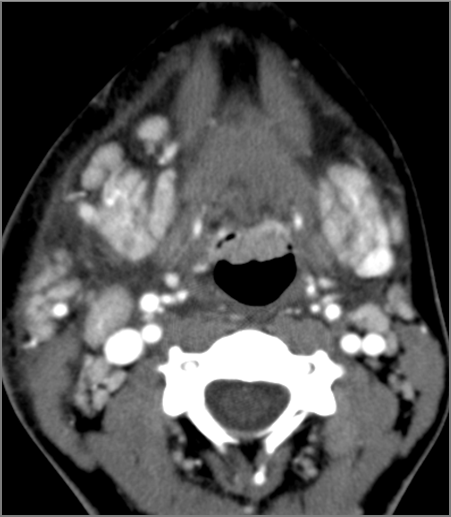

There is excessive enhancement or thickening of the mucosa or hypertrophy of the palatine or lingual tonsillar tissue or the lymphoid tissue along the glossotonsillar sulci and posterior pharyngeal wall. [Yes/No]

There is abscess relatively centrally within the lymphoid tissue of the palatine tonsil. [Yes/No]

There is abscess at the periphery of the lymphoid tissue of the palatine tonsil within the potential peritonsillar space of the palatine tonsil within the potential peritonsillar space

[Yes/No]

There is edema/abscess within the fat of the adjacent parapharyngeal and retropharyngeal spaces. [Yes/No]